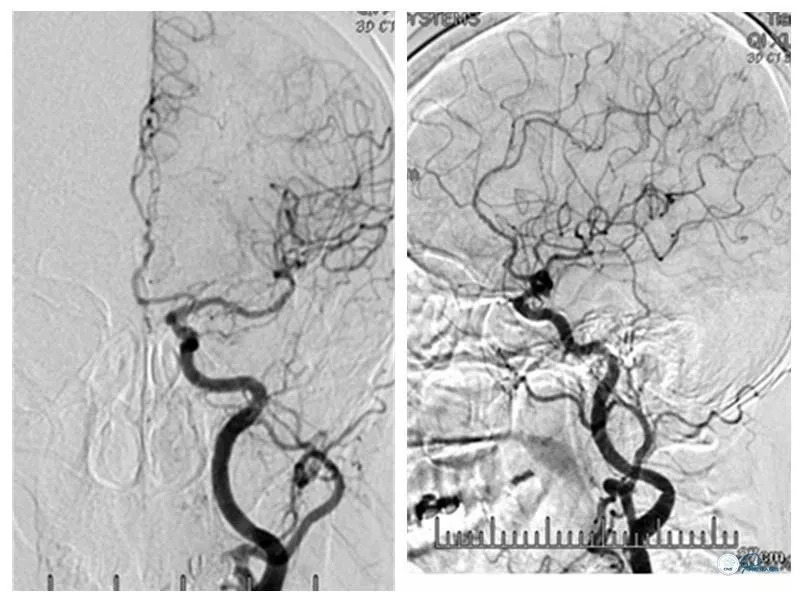

MRA及CTA示右椎动脉优势,双椎动脉V4段-基底动脉汇合处狭窄(图2、3)。

图2

图3